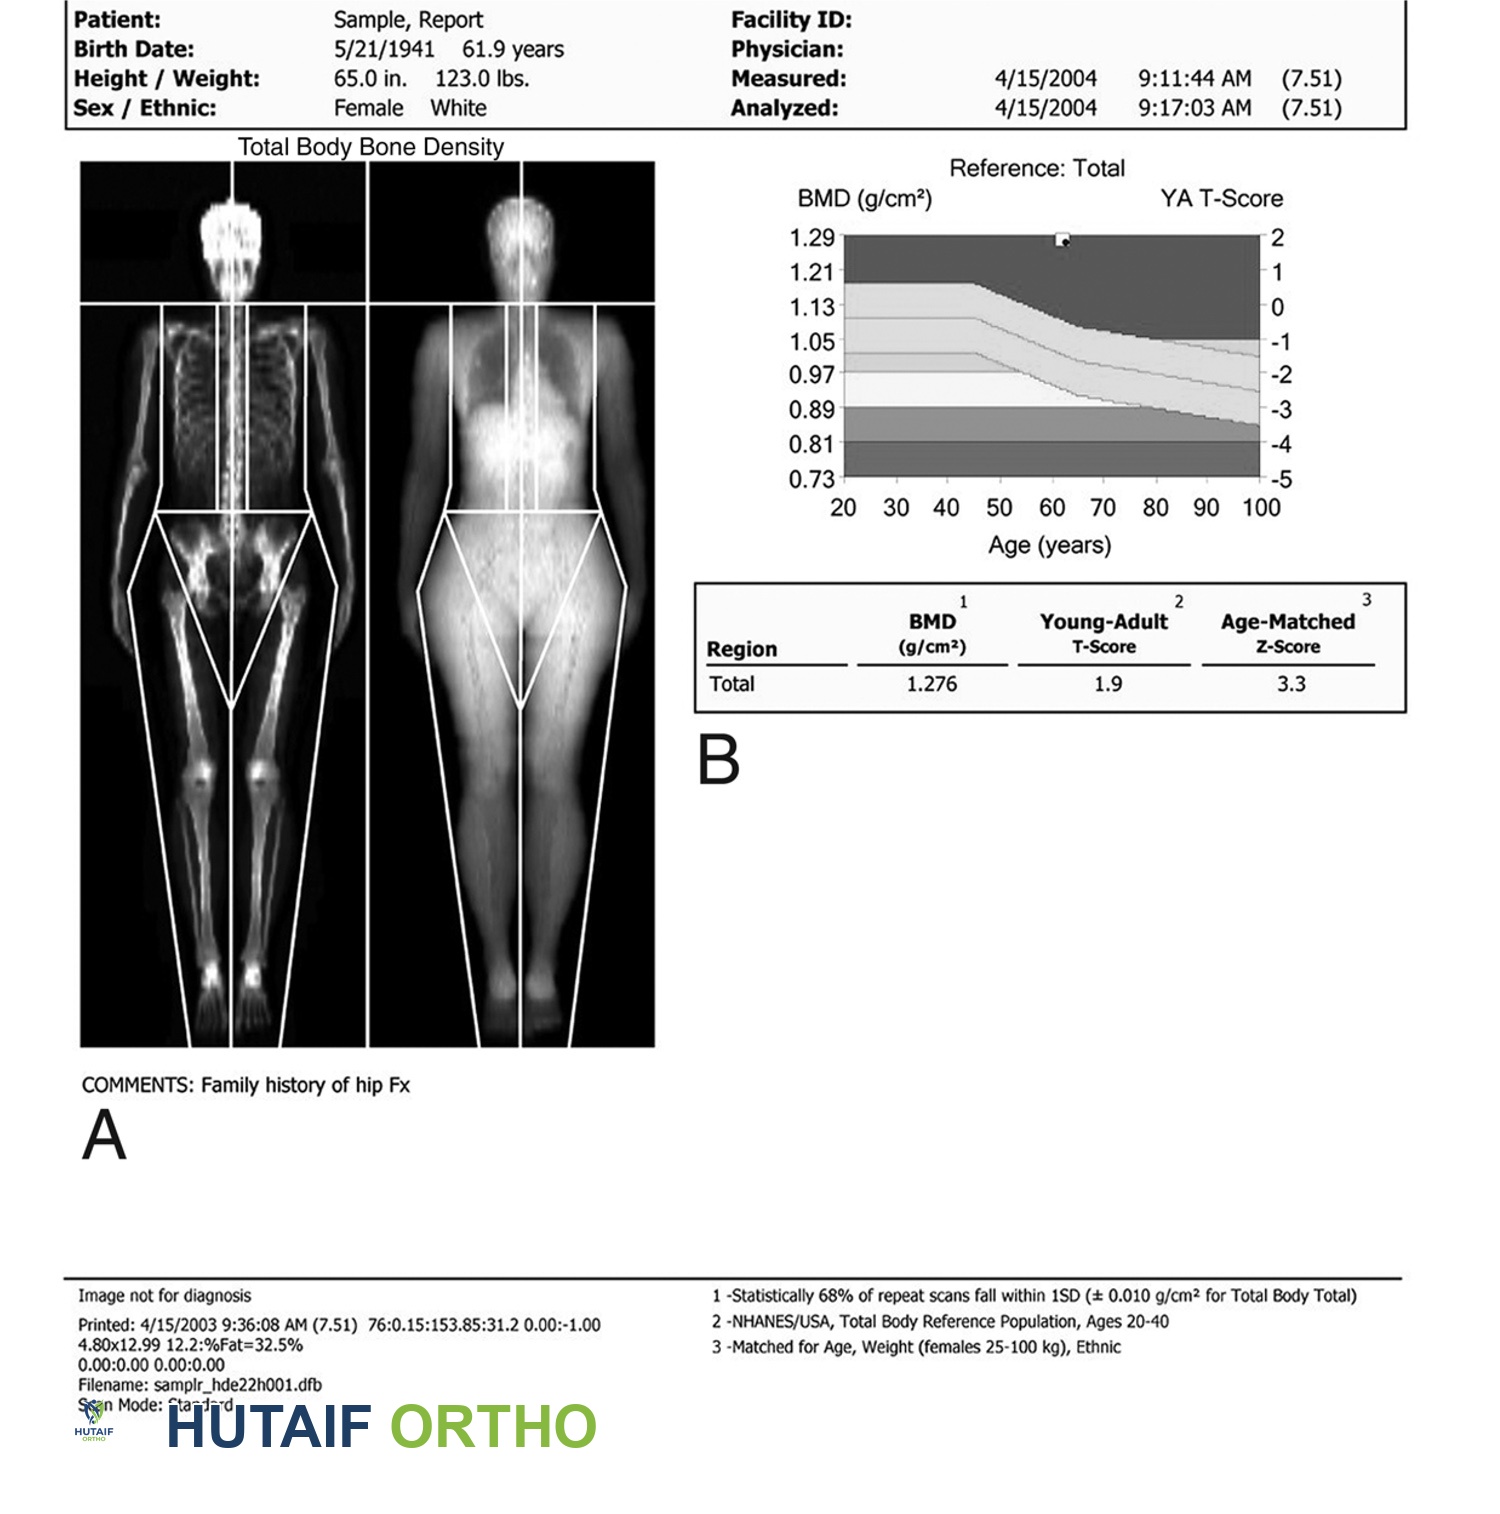

فحص امتصاص الأشعة السينية ثنائي الطاقة (DXA)

يُعد فحص امتصاص الأشعة السينية ثنائي الطاقة (DXA) "المعيار الذهبي" لاختبار كثافة المعادن في العظام.

مُعاد إنتاجه بإذن من JF Sarwark, ed: Essentials of Musculoskeletal Care, ed 4. Rosemont, IL, American Academy of Orthopaedic Surgeons, 2010